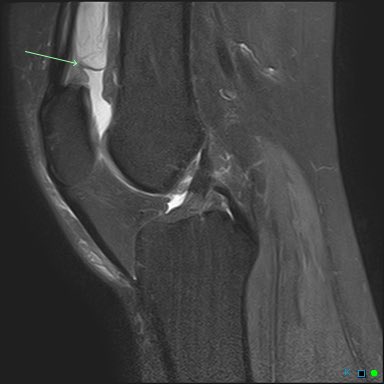

Consent ✅ Right hip pain & stiffness Both hip joints show OA changes - but R more advanced than L Why?